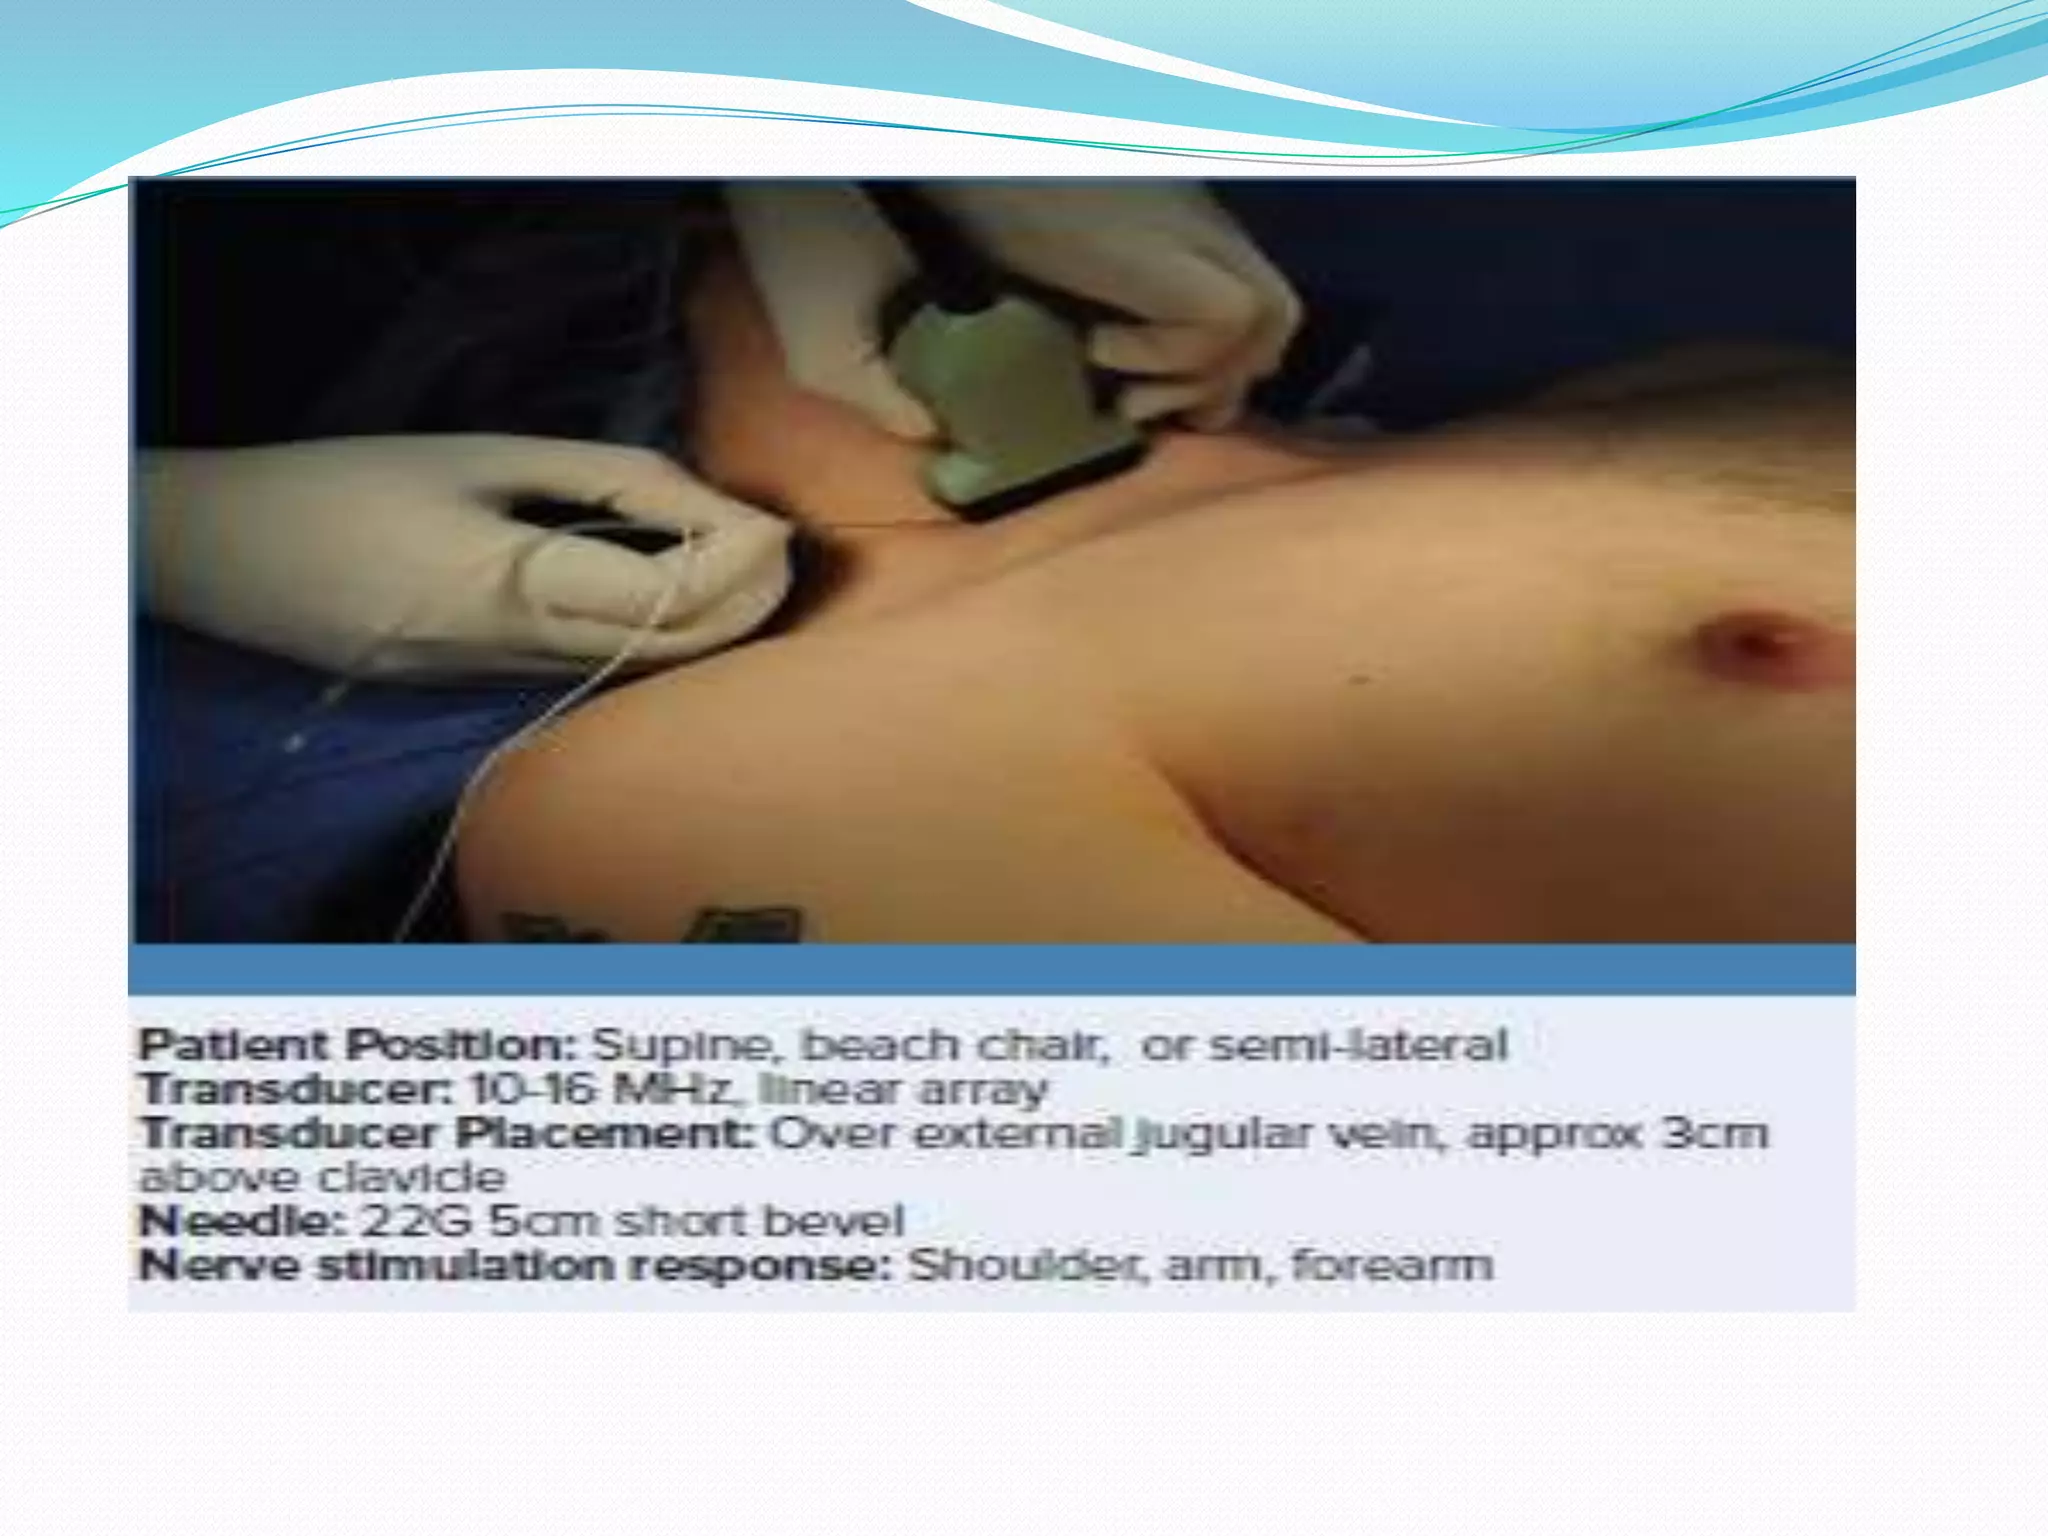

This document provides an overview of brachial plexus anatomy and techniques for brachial plexus nerve blocks. It begins with a description of the brachial plexus formation from cervical and thoracic nerve roots and its branching pattern. Four main approaches for brachial plexus nerve blocks are described: interscalene, supraclavicular, infraclavicular, and axillary. Details are provided on the anatomy and techniques for performing interscalene and supraclavicular brachial plexus blocks. Ultrasound guidance is discussed as an advancement which allows real-time visualization of needle and nerve. Complications are also summarized.